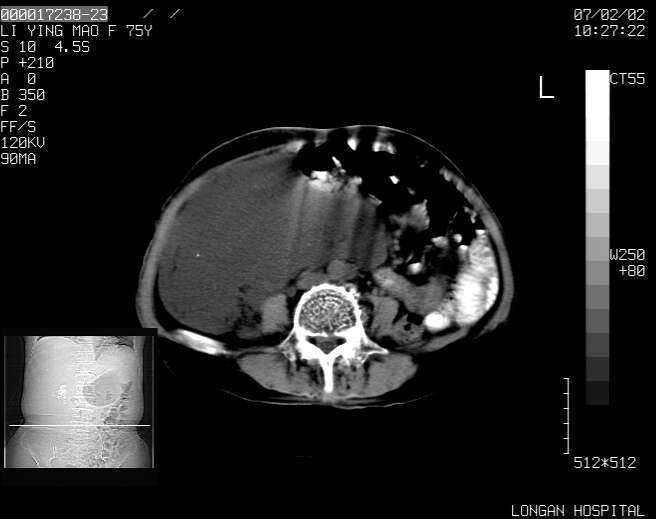

以下是引用dyqct在2007-2-10 8:53:00的发言:[br]考虑:1、肝脏多发囊肿[br] 2、左肾囊肿,右肾多发结石并积水。[br] 3、右胸少量积液。[br] 4、右肾周包裹性积液或淋巴管瘤(有见缝就钻的征象、薄隔、小结节状钙化)?[br] 5、腰椎动脉瘤样骨囊肿?[br] [br] [br]